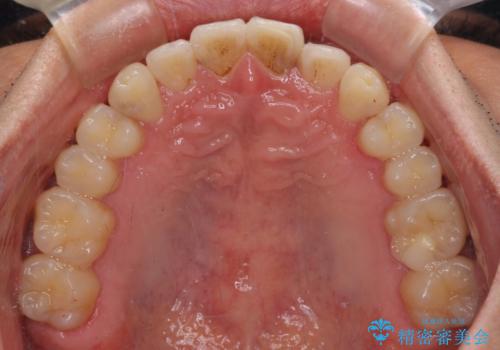

気になる前歯のデコボコをインビザラインで解消

- 前歯のデコボコを気にして来院された患者様です。

主に下顎歯列全体の後方移動とIPR(歯と歯の間を削る)によってデコボコが解消するように設計し、インビザラインにより治療を行うこととしました。

インビザライン矯正特有の、治療後半で前歯のみが強く接触する症状が発現し、咬み合わせ改善に期間を要することとなりました。